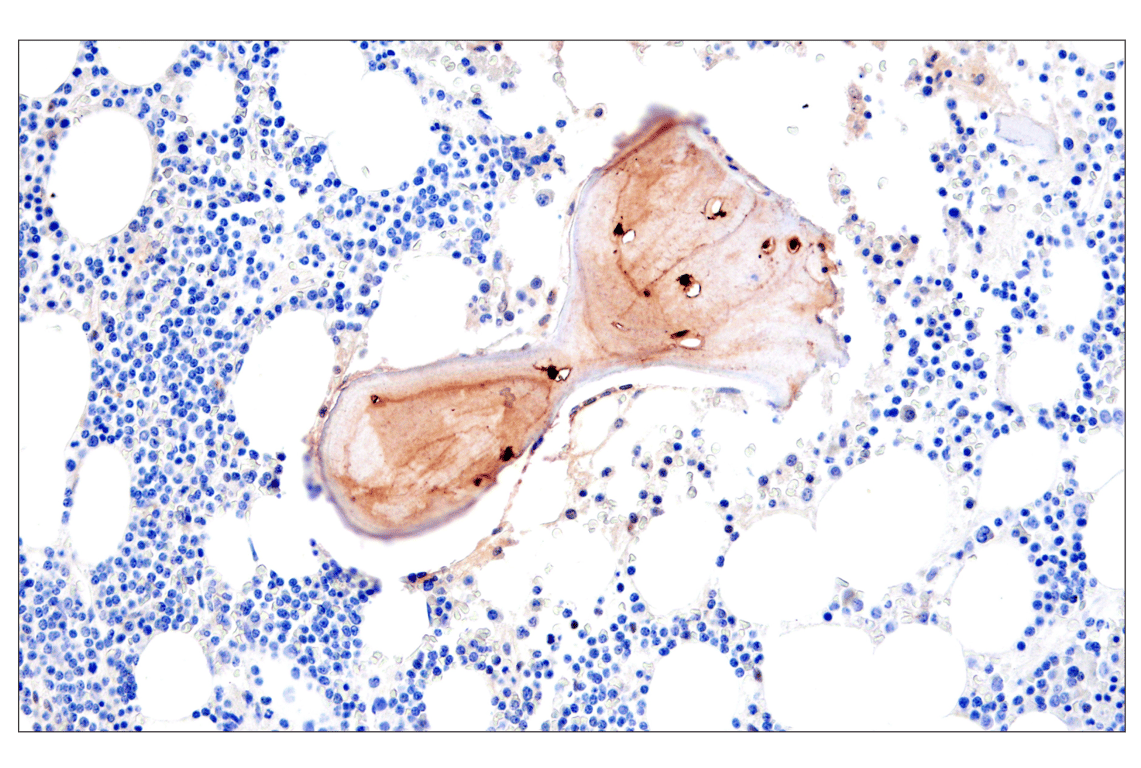

Immunohistochemical analysis of paraffin-embedded human metastatic adenocarcinoma in bone using Osteocalcin (E8B9X) Rabbit mAb.

Immunohistochemistry Image 3: Osteocalcin (E8B9X) Rabbit Monoclonal Antibody